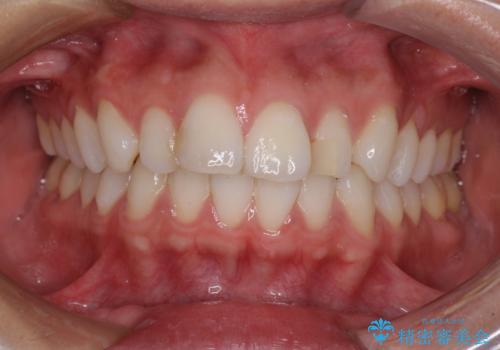

唇を閉じやすく 出っ歯の抜歯矯正

- くちばしのような前歯の突出感を気にして来院された患者様です。

上下左右第一小臼歯4本を抜歯して、積極的に口元を引っ込めるよう、ワイヤー装置にて矯正治療を行うこととしました。

抜歯矯正を行ったことで、顎先のつっぱり感や口元の閉じにくさを解消することができました。